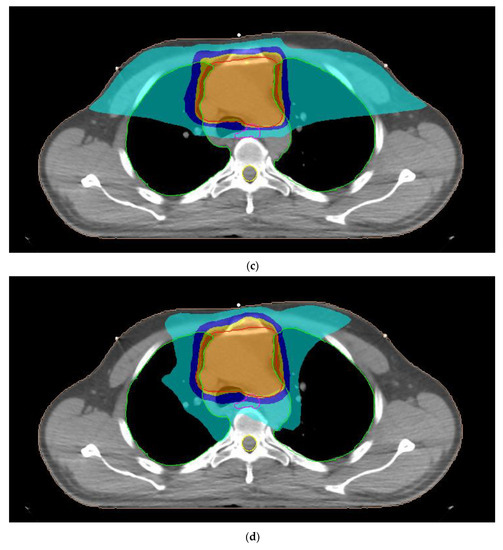

A typical dose distribution of a patient with thymoma from 3D-CRT, 7F-IMRT, 5F-IMRT, FA-VMAT and PA-VMAT plans is presented in Figure 1. The dose parameters for the PTV are summarized in Table 3. The mean TC, HI and CN for 3D-CRT were 58.4%, 1.11 and 0.48, respectively. The corresponding parameters for IMRT plans reached 95.6%, 1.06 and 0.83 whereas those for VMAT plans were up to 95.7%, 1.07 and 0.82.

Figure 1.

Typical dose distribution around the target volume, shown in red color, for (a) three-dimensional conformal radiotherapy, (b) seven-field intensity modulated radiation therapy, (c) five-field intensity modulated radiation therapy, (d) full-arc volumetric modulated arc therapy and (e) partial-arc volumetric modulated arc therapy techniques of a male patient with thymoma. The 95%, 90%, 75% and 45% isodoses are presented with orange, dark yellow, dark blue and light blue colors, respectively. The lungs, esophagus and spinal cord are denoted by the green, pink and yellow contours, respectively.